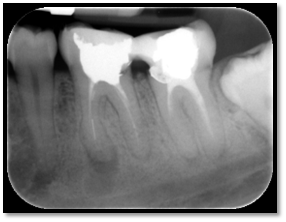

Molar endodontics

Pre-operative

Post-operative